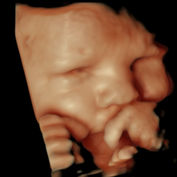

Nuestra misión en First Sight Frederick es brindarles a los futuros padres una experiencia única e inolvidable al ofrecer tecnología de ultrasonido 3D, 4D, 5D y 6D/HD de última generación para capturar imágenes detalladas de su feto. Estamos comprometidos a crear un ambiente cálido y acogedor para nuestros clientes, al mismo tiempo que brindamos un servicio al cliente excepcional y mantenemos los más altos estándares de seguridad y precisión en nuestros servicios de imágenes. Nuestro objetivo es ayudar a los padres a vincularse con su bebé antes del nacimiento y crear recuerdos duraderos que serán apreciados durante toda la vida.